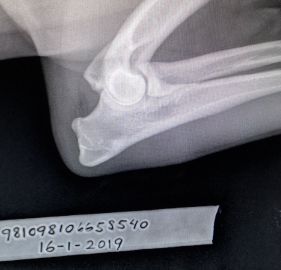

HD : A/A

AD : 0/0